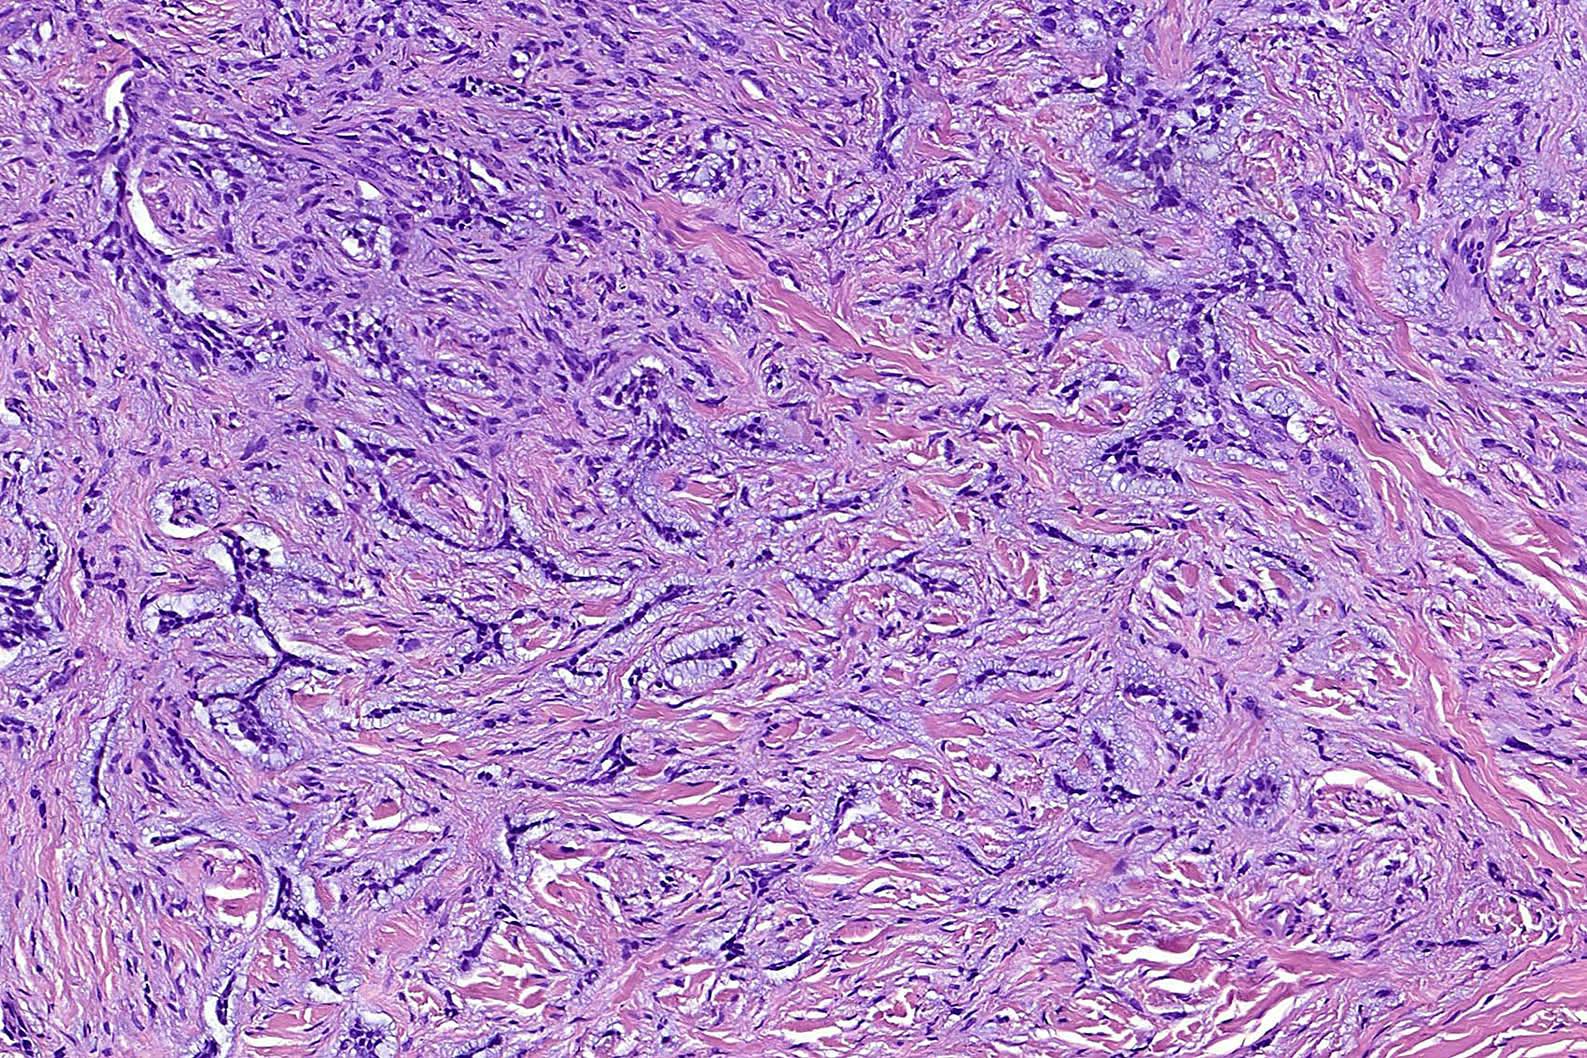

- Morpheaform (sclerosing, morphoeic) BCC

- Thin strands and nests of basaloid cells

- Limited peripheral palisading

- Stroma is dense and sclerotic

- Extensive spread

- Perineural invasion can be seen